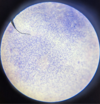

Leishmania sp.: Amastigotes

Divided & intracellular - Only in macrophages